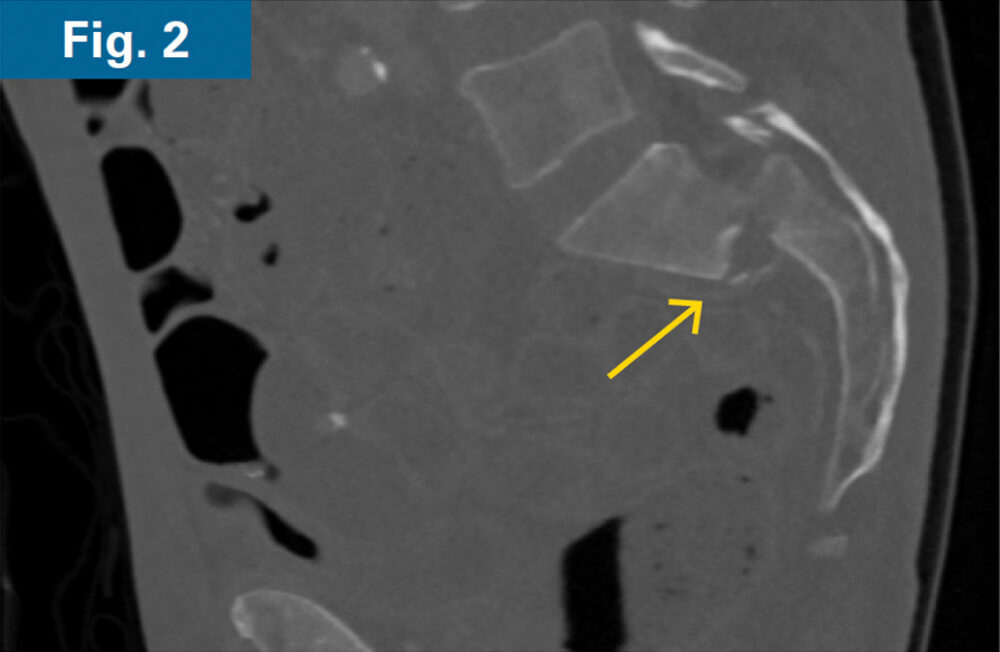

• 62 y/o male with COPD and 1 month old sacral U-type fracture after motorcycle crash (Figs. 1 and 2)

• Comminution and displacement of the right side component of his sacral U-type fracture significantly decreased the osseous corridor for placement of trans-sacral style screw in S1 requiring an iFuse TORQ® implant to provide sufficient fixation